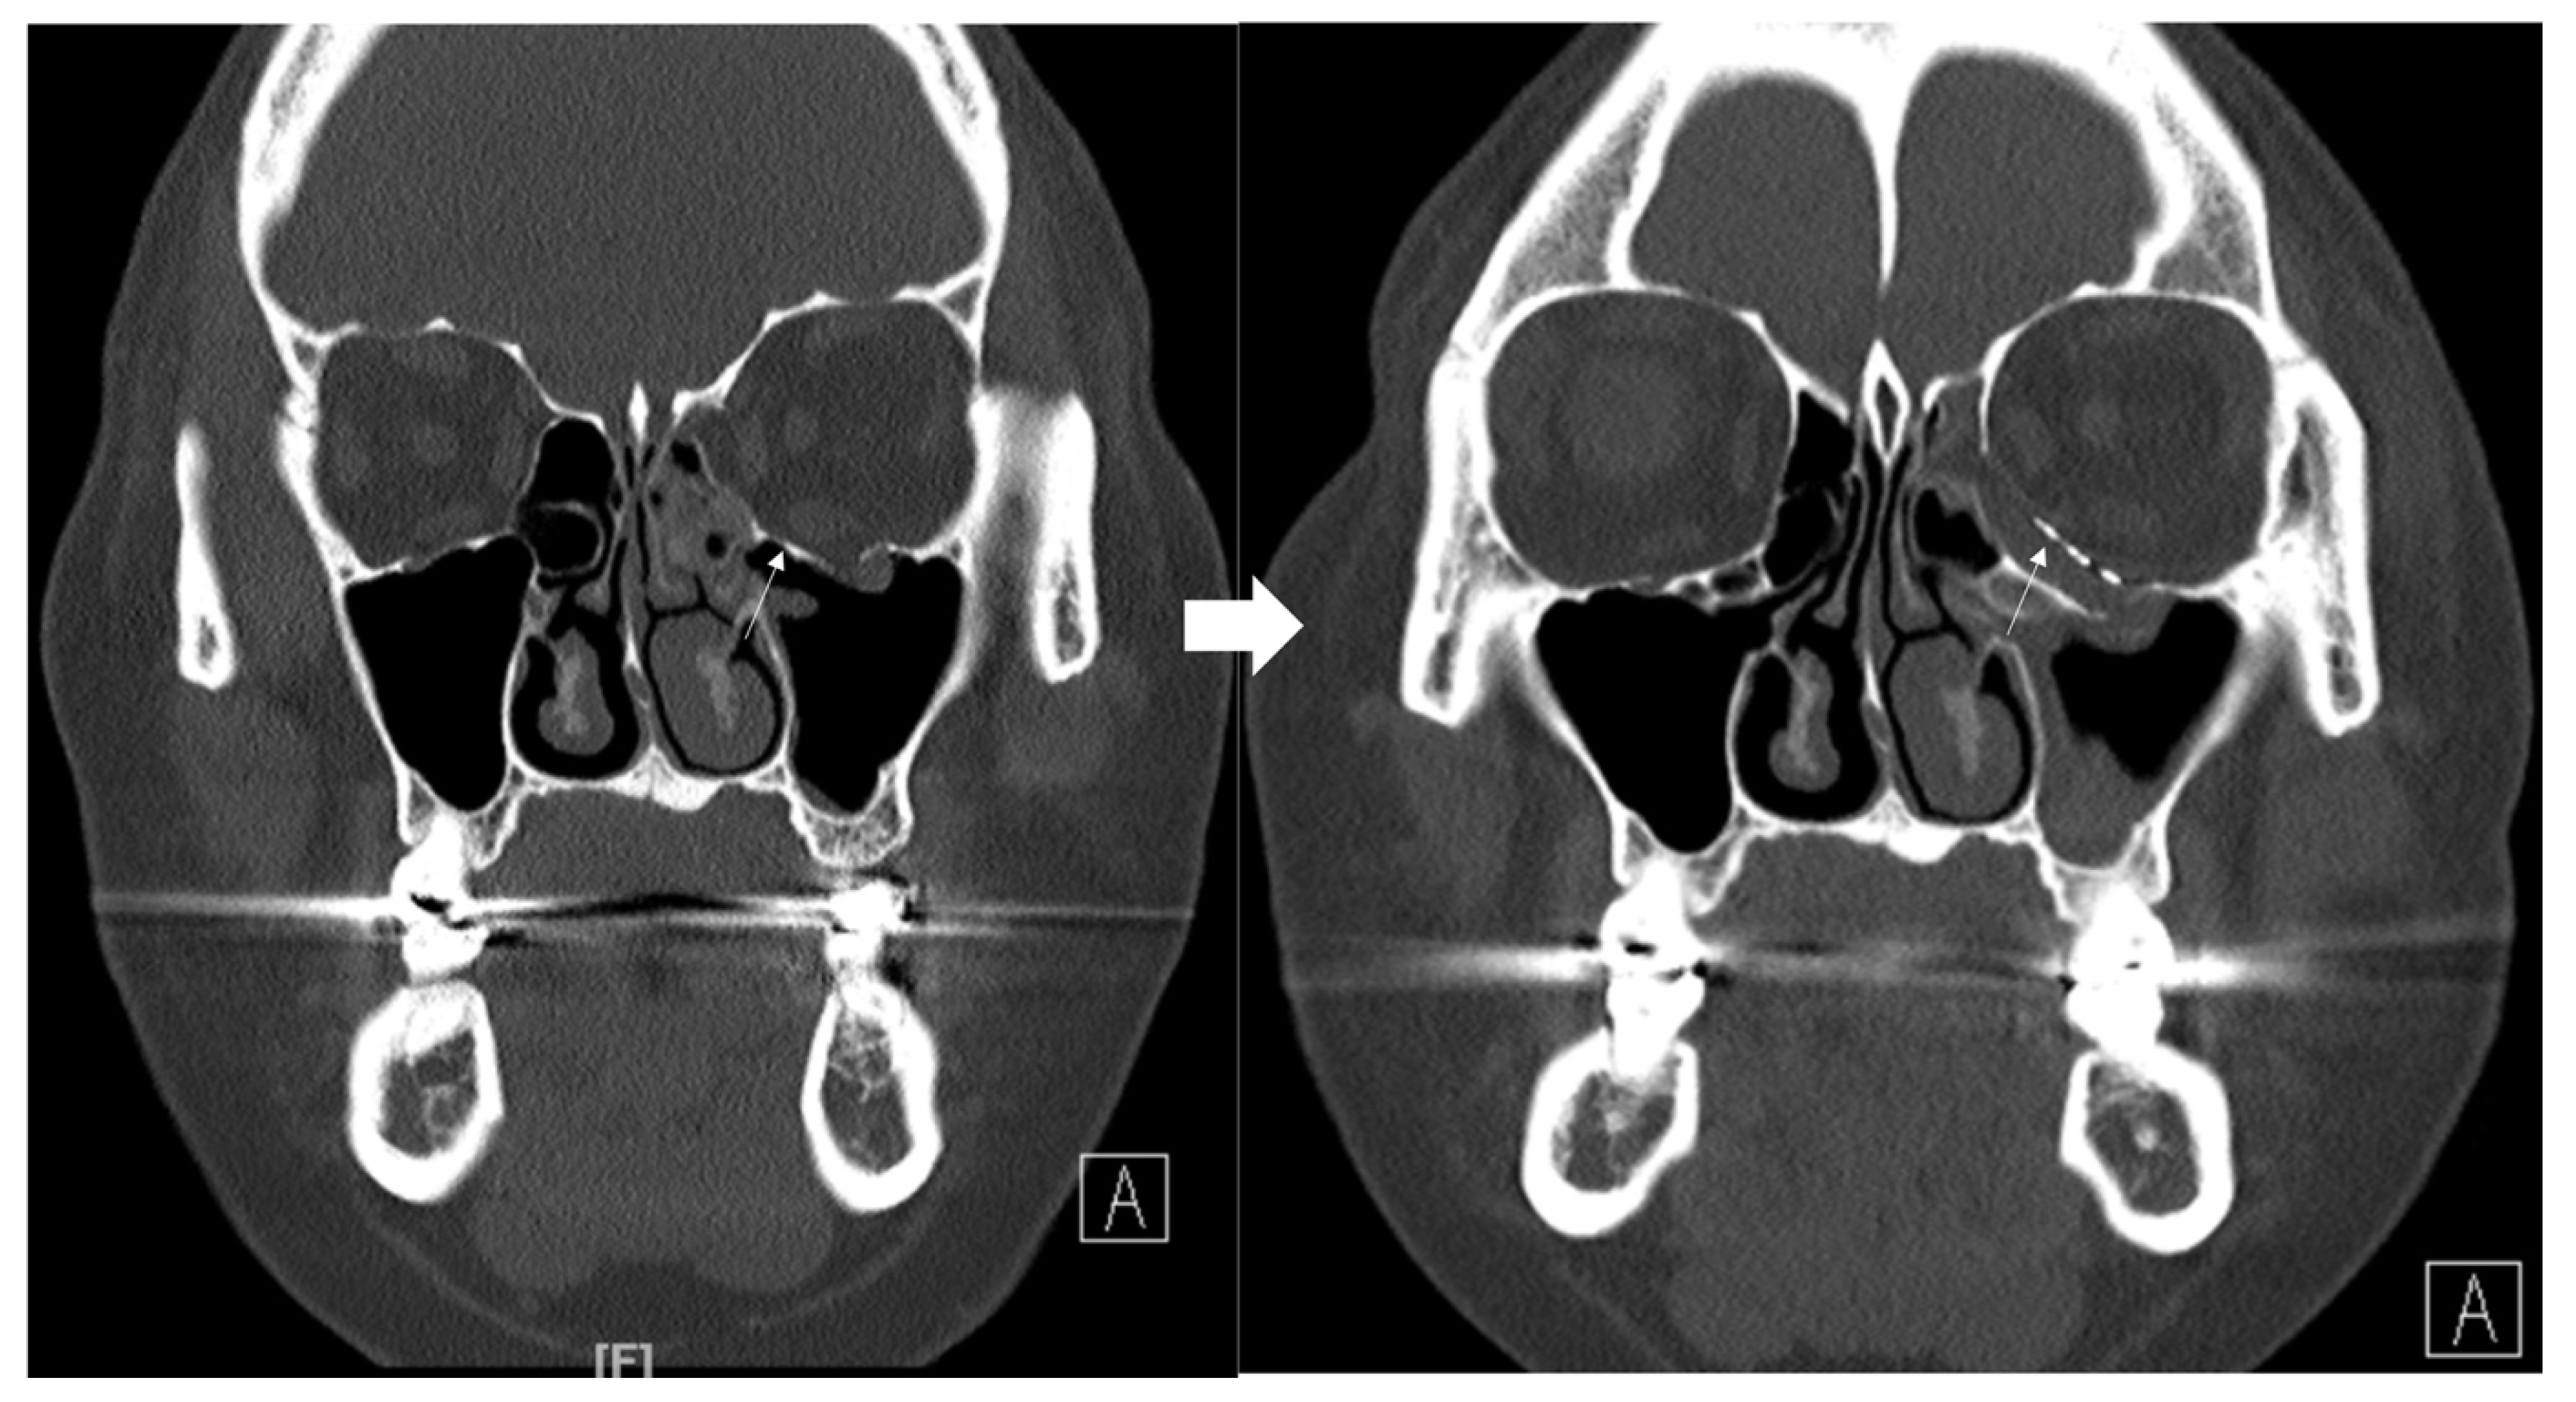

A 34-year-old female patient came to our clinic with left eyeball swelling and ecchymosis caused by a direct trauma to the eyeball. The patient complained of pain and discomfort with eyeball movement (Figure 5). We surgically approached the medial orbital wall fracture two days after the accident. After the subciliary incision, the fracture was exposed. The titanium-reinforced porous polyethylene (TR-PPE) plate was placed on the fracture site using a single screw at the inferior orbital rim (Figure 6). The patient was discharged on postoperative day 2 with significantly improved pain and discomfort.

Figure 5. Case 3. Preoperative facial CT scan (coronal and axial view) of the 34-year-old female patient with left medial orbital wall fracture (white arrow). The fracture sites were designated with white arrows.

Figure 6. Case 3. Follow-up facial CT finding (coronal and axial view) of the same patient. The titanium-reinforced porous polyethylene (TR-PPE) plate was placed on the inferomedial orbital wall using a single screw at the inferior orbital rim. (White arrow).